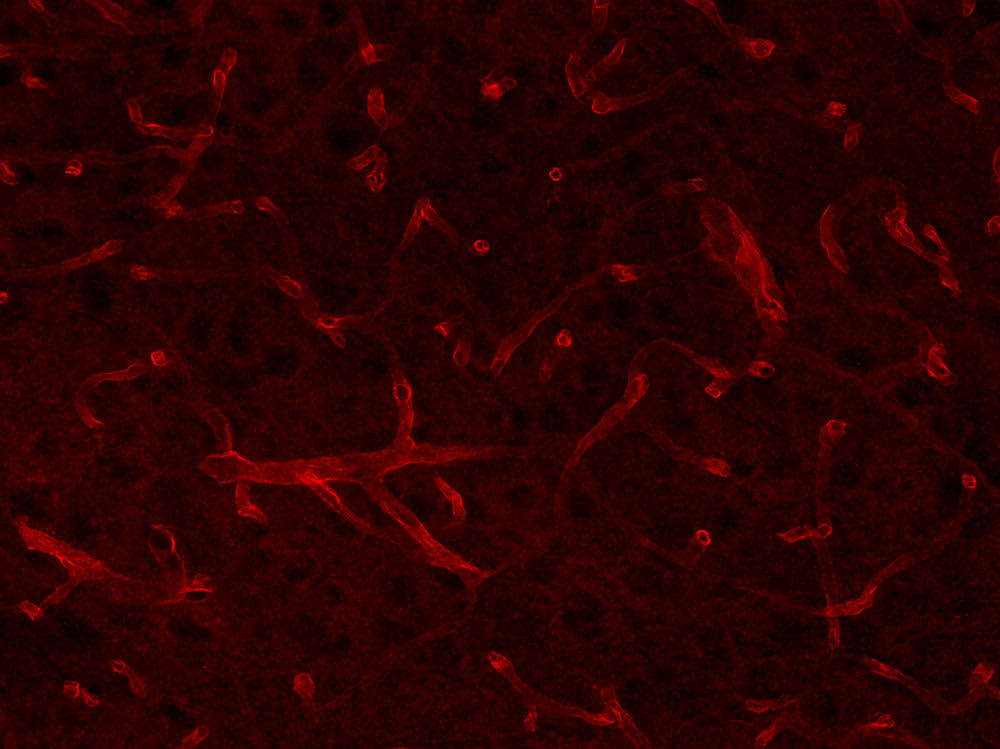

Aquaporin4, Polyclonal Antibody

- Application:

- Immunocytochemistry, Immunohistochemistry